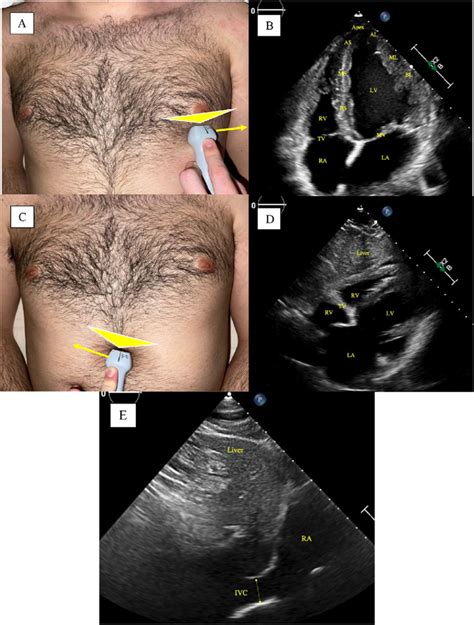

Alright team, let’s get down to the nitty-gritty of probe placement for that awesome 5-chamber view . This is where the magic happens, guys! You’ll typically want to start at the apical window . Think of the apex of the heart – that’s your target zone. Position the transducer at the left lateral chest wall , usually between the fifth and sixth intercostal spaces . Sometimes, you might need to go a little higher or lower, or more medially or laterally, depending on your patient’s body habitus. The key here is to aim the transducer towards the patient’s right shoulder . This orientation is super important because it allows the ultrasound beam to pass through the heart without being significantly blocked by the lungs or ribs. Imagine you’re trying to get a direct line of sight to the heart’s core. Now, the initial placement might give you a 4-chamber view. That’s a great starting point! From there, you’ll need to make subtle adjustments. The goal is to rotate the transducer slightly counter-clockwise (think of the indicator dot on the probe pointing towards the patient’s left axilla) while maintaining that apical position. This subtle rotation is what brings the aortic valve into view, effectively transforming your 4-chamber view into the coveted 5-chamber view. You’re essentially peeking over the left atrium to get a glimpse of the aortic outflow tract. Remember, you’re looking for a clear image of the left ventricle, left atrium, mitral valve, and the aortic valve, all in the same plane. The interventricular septum should be on your left, and the left atrial wall on your right. The aortic valve will be seen superiorly and slightly to the left of the mitral valve. Fine-tuning is everything. Small tilts and shifts can make a huge difference in image quality. Don’t be afraid to gently fan the transducer or adjust the depth and gain controls to optimize what you’re seeing. The goal is a symmetrical-looking left ventricle, with well-defined walls and clear visualization of all four chambers and the aortic valve. Practice makes perfect, so keep trying different angles and positions until it feels intuitive. You’ll know you’ve got it when you can see the mitral valve leaflets opening and closing, and the aortic valve opening during systole. This view is crucial for assessing mitral regurgitation, aortic stenosis, and the overall function of the left side of the heart. It’s the integration of anatomical understanding with hands-on manipulation that truly elevates your echocardiography skills. Patient positioning can also play a role; a left lateral decubitus position often facilitates better apical access. However, always adapt to the patient’s ability to tolerate different positions. The depth setting on the ultrasound machine is critical; you want to ensure the entire heart is displayed without excessive surrounding tissue. Similarly, the gain settings need careful adjustment to differentiate between the endocardium, myocardium, and blood pool, avoiding both under-gaining (poor visualization) and over-gaining (flash artifacts or loss of detail). Patience and persistence are your best friends here. It might take a few tries, or even a few minutes, to achieve the optimal view, especially in patients with certain body types or lung disease that can impede ultrasound transmission.